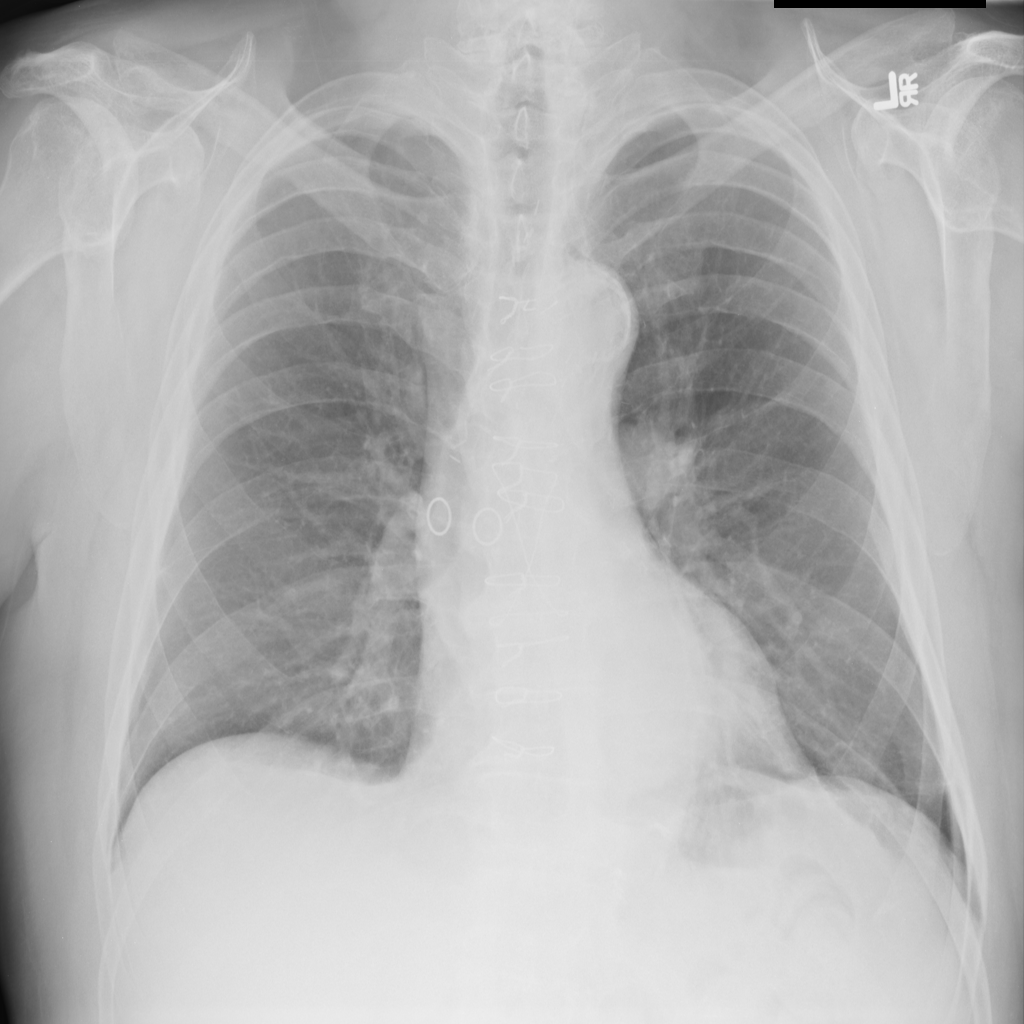

PAT-DB80 · IMG-000Atelectasis

PAT-DB80 · IMG-000

PA